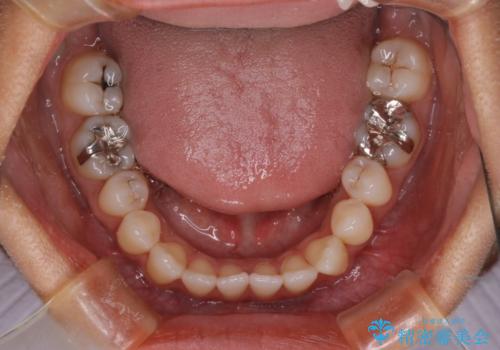

- 開咬を主訴に来院されました。前歯部に開咬、右側大臼歯部にクロスバイトが認められます。ワイヤー矯正の審美装置で治療し、ゴム掛けを行いながら噛み合わせを改善しました。

主訴である開咬と右側大臼歯部クロスバイトを改善でき、しっかりと噛むことができるようになりました。